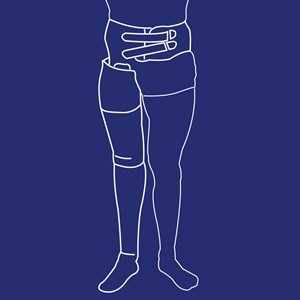

Knæ-Ankel-Fod Ortose (KAFO)

Type: pdf

Størrelse: 1539 KB